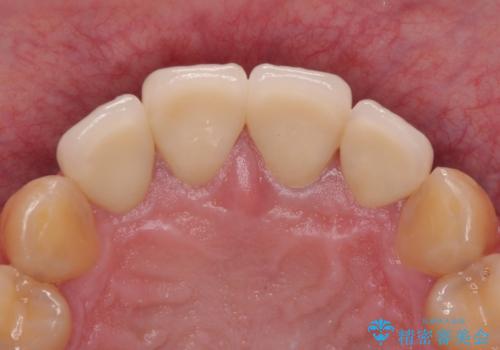

審美面、機能面共に大変満足していただきました。今後は左下の欠損部にインプラント治療を行っていく予定です。